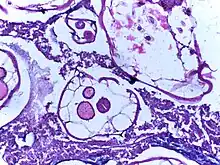

Specific helminths can be identified through microscopic examination of their eggs (ova) found in faecal samples. The number of eggs is measured in units of eggs per gram.[34] However, it does not quantify mixed infections, and in practice, is inaccurate for quantifying the eggs of schistosomes and soil-transmitted helminths.[35] Sophisticated tests such as serological assays, antigen tests, and molecular diagnosis are also available;[34][36] however, they are time-consuming, expensive and not always reliable.[37]